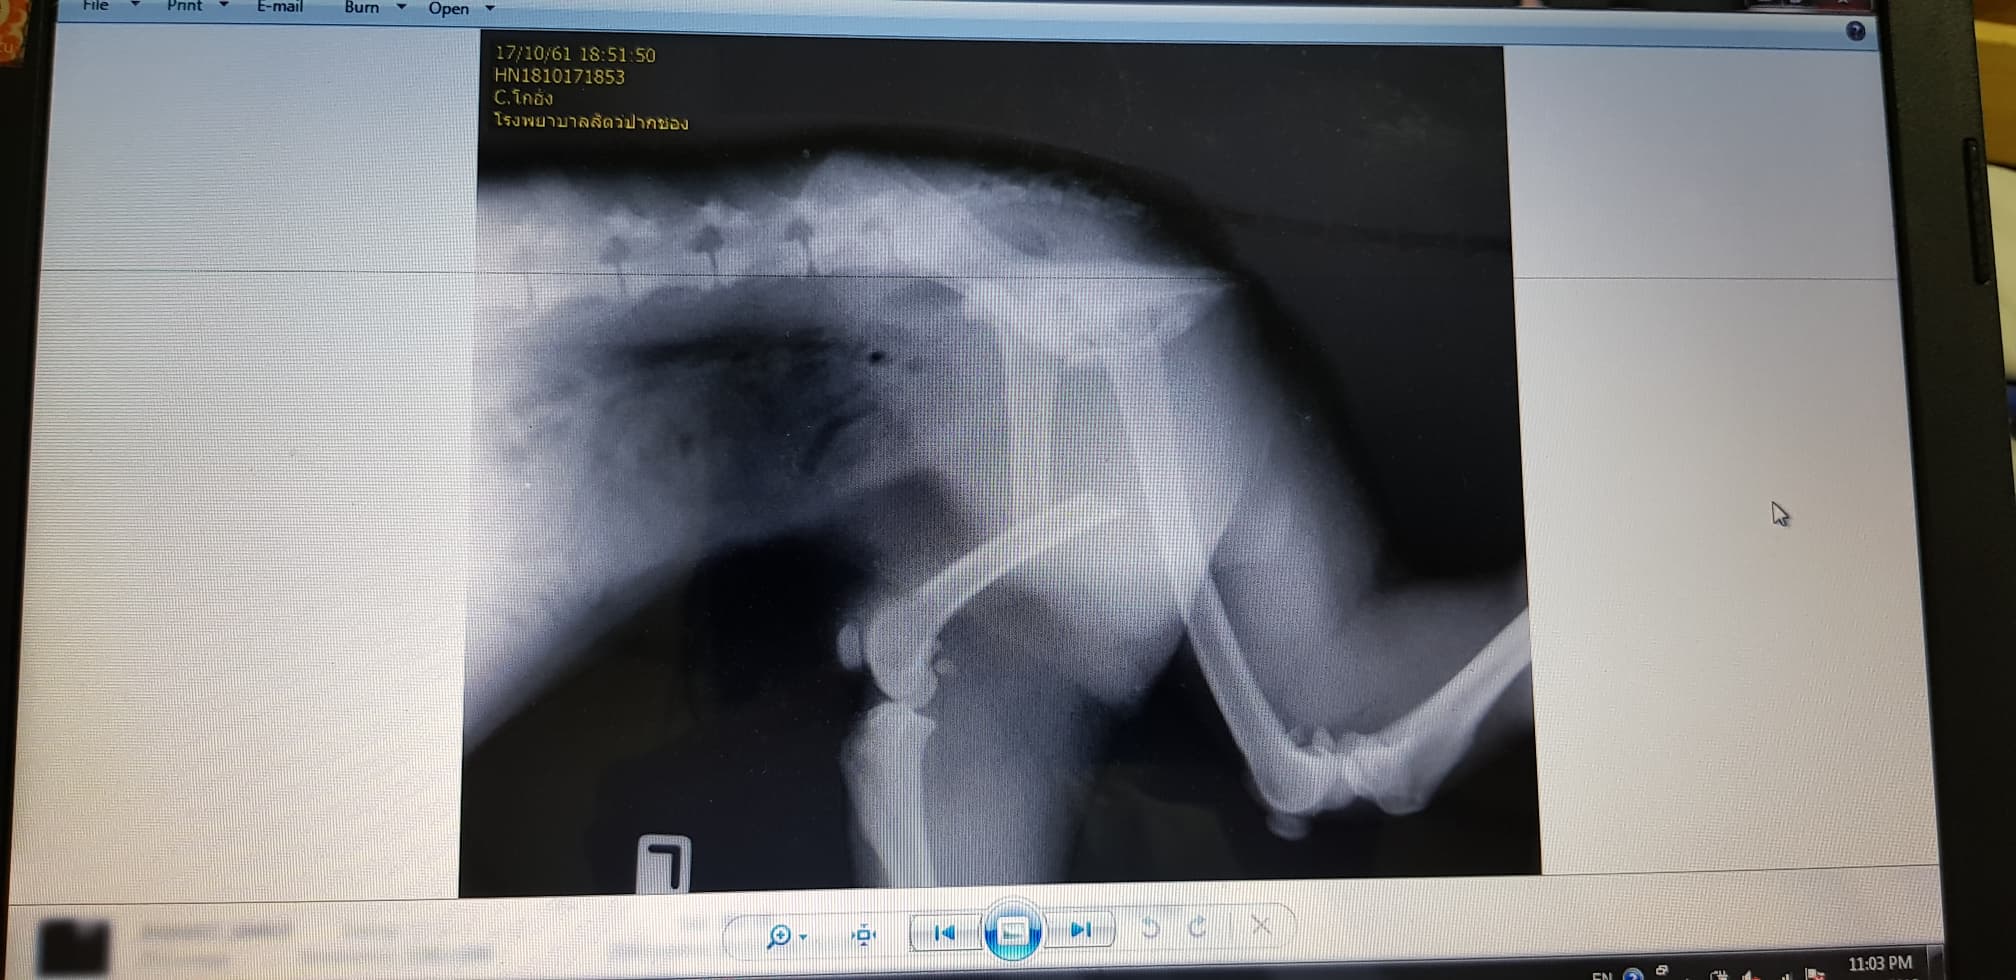

น้องเดินสามขา ท่าทางจะเจ็บมาก เลยรีบพาไปเอ็กซ์เรย์ ปรากฎว่ากระดูกขาหลังหัก กับ สะโพกหลุด ฮืออ

ต้องขอขอบคุณคุณหมอที่รับผ่ามากๆเลยค่ะ ทันทีที่ส่งภาพเอ็กซ์เรย์ให้ดูในไลน์ คุณหมอก็รีบโทรไลน์กลับ ถามอาการน้อง